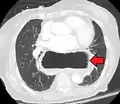

A hiatal hernia as seen on CT

A large hiatal hernia as seen on CT imaging